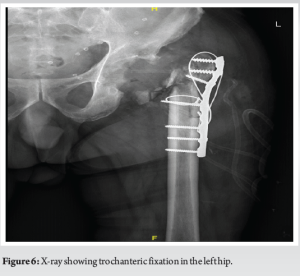

Stage 1 surgery was done via a posterior approach through the previous scar. Intraoperatively, after opening the fascia lata, we noticed a large soft tissue mass around the trochanter and acetabular region which was dark reddish brown in color. There was severe osteolysis around the acetabulum and trochanteric region. After the excision of the soft tissue mass, the material was sent for histopathology and culture (Fig. 5b). The acetabular component was completely loose, so it was removed along with the ceramic liner (Fig. 5a). There was no damage seen on the ceramic femoral head and acetabular liner. The trunnion of the femoral stem was normal. Since the femoral stem was well integrated, extended trochanteric osteotomy was done to remove the femoral stem. Extended trochanteric osteotomy was closed with encircling wiring and plating (Fig. 6). His histopathology reports showed fibrin, proliferating fibroblasts, hemosiderin-laden macrophages, lymphocytes, and chronic granulation tissue findings suggestive of pseudotumor formation. There was no evidence of malignancy (Fig. 7).